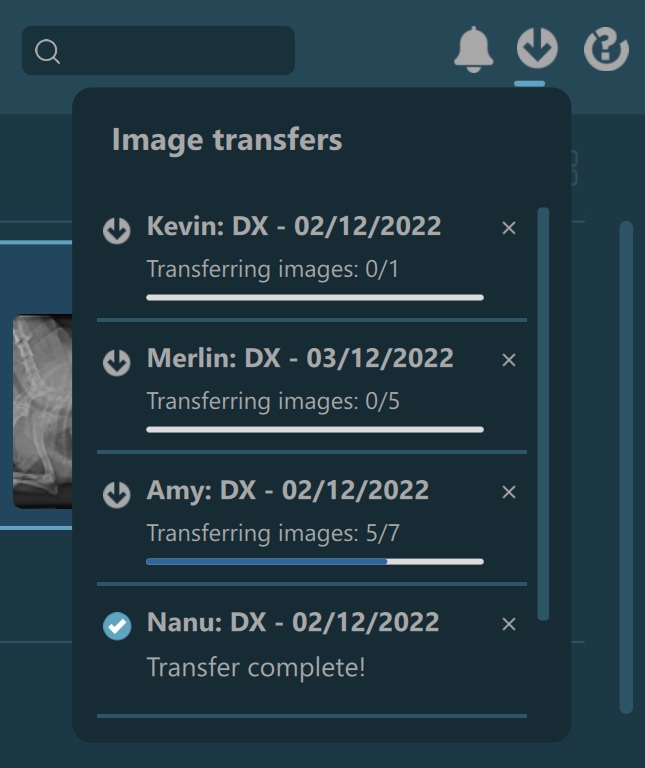

Servers configured to transfer images will save the DICOM files in the selected VisioVIEW data directory specified in the advanced settings. When using these servers, the top study browser toolbar contains an additional

Transfers button in the top right corner, indicating the ongoing and/or finished transfers of images, grouped by studies.

To access the current ongoing and/or finished transfers, simply press the button which will open the related popup. The latest requested transfers of images will always be shown at top of the list in the popup. The popup will show a maximum of

20 study transfers, and if more are required to be added, the software automatically removes the oldest ones from the list to accommodate space for new entries. Manually remove an entry from the popup by simply pressing the x button.

The overall progress of the ongoing transfer of images is indicated below the button, while the progress of each study is indicated when opening the popup.

Completed transfers of images are indicated in two different ways in VisioVIEW. The Transfers button has a blue dot in the top right corner to indicate unopened completed transfers, which is automatically removed as soon as the user opens the

popup. In addition, as soon as a transfer of a study is completed, a notification of the completed transfer pops up in the bottom right corner of the Preview Pane, with the latest notification stacking up above the older ones. The notifications

are visible for about three seconds before automatically disappearing.